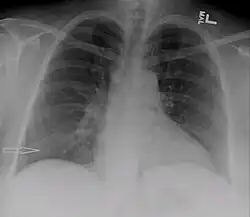

Right sided pleural effusion caused by urinothorax

Urinothorax (pl. urinothoraces) is defined as urine in the fluid-filled cavity that surrounds the lungs.[1] It is usually caused by obstructive uropathy. It is mainly diagnosed by analyzing the pleural fluid. Treatment involves treating the underlying condition, which typically results in resolution of the urinothorax. It is an extremely rare cause of pleural effusion.[2]